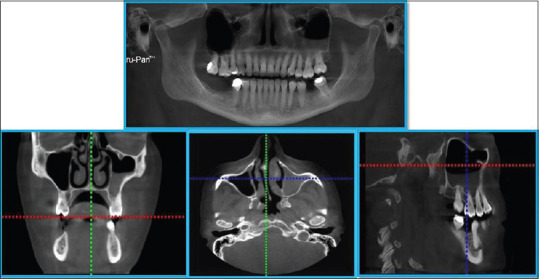

Abstract Image